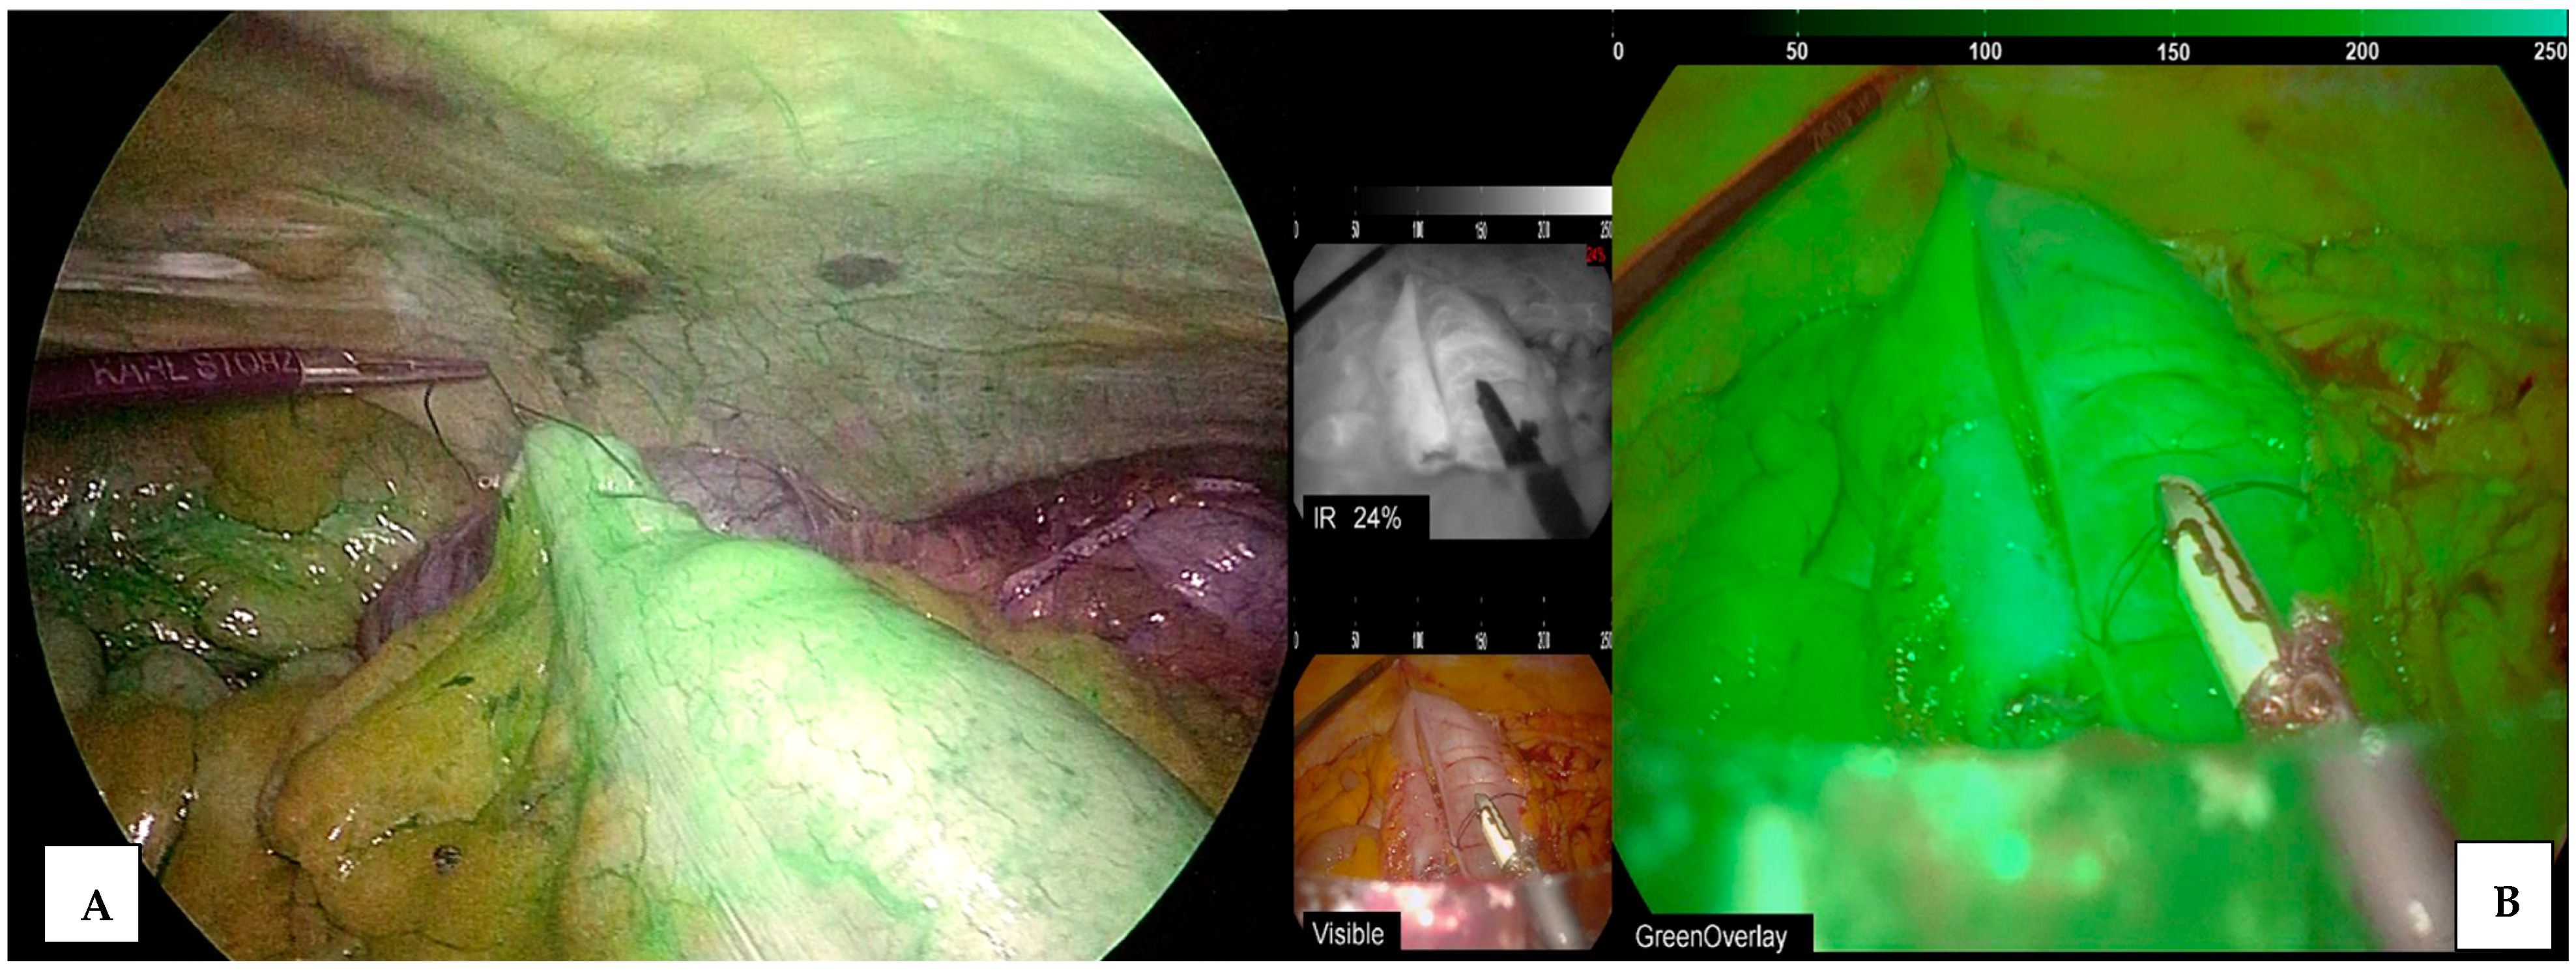

3.4. ICG in Laparoscopic Cholecystectomy